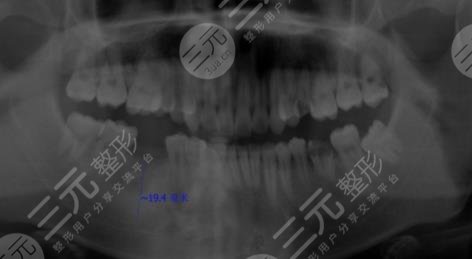

因为我真的十分喜欢吃糖,也就是很喜欢甜食,几乎每天都有很多的糖摄入,有的时候连吃米饭我想要吃甜的,这就导致了我的年纪轻轻牙齿就蛀了,因为糖吃多了,刚开始的时候还只是进行补牙,但是随着时间越来越久,我的牙齿的孔洞越来越大,然后没有办法就是拔掉了,我想着一直去补也不是问题,就跟父母商量之后,来到了镇江口腔医院进行种植牙。

医生看了我的牙齿情况之后,为我判断了几颗比较需要进行种植牙的地方进行了拔除。大概在拔完牙,一星期后我进行了种植牙,刚种上的时候还是觉得挺不舒服的,但是随着时间的推移,我逐渐适应了自己的种植牙,并且种植的牙齿比之前更加洁白,它不单单解决了我的口腔问题,还让我整个人的气质都上升了不少呢。